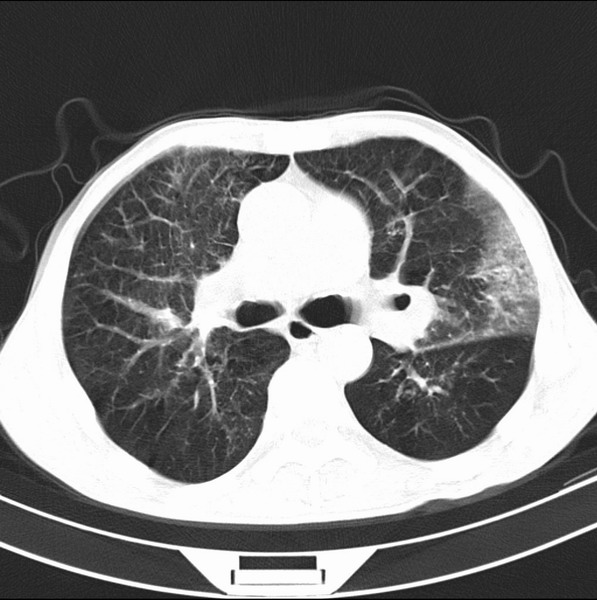

标题: CT19600:能否诊断为转移?

女、55

3年前盲肠癌、一年半前诊断膀胱癌,现在呼吸困难,临床考虑为肺转移

请问胸部ct如何诊断?能否排除淋巴管炎,纵隔窗没有问题。

考虑间质性病变,癌性淋巴管炎可能.

转移,癌性淋巴管炎。

建议抗炎后复查,不除外癌性淋巴管炎。

炎性并间质纤维化,请询问病史,如用过平阳霉素或其他化疗药.可能为药物引起的间质纤维化.